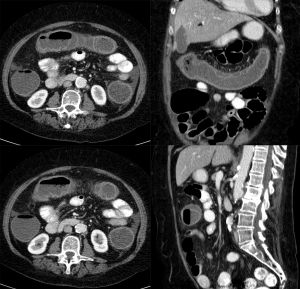

- CT Abdomen and Pelvis with Contrast to evaluate for intestinal inflammation.

- May consider CTA to rule out mesenteric ischemia, but will rarely show large vessel occlusion.

- Diagnosis is typically determined on abdominopelvic CT

- Ischemic colitis most likely when found in splenic flexure or sigmoid colon. Ischemic colitis unlikely for colitis that localizes to other areas